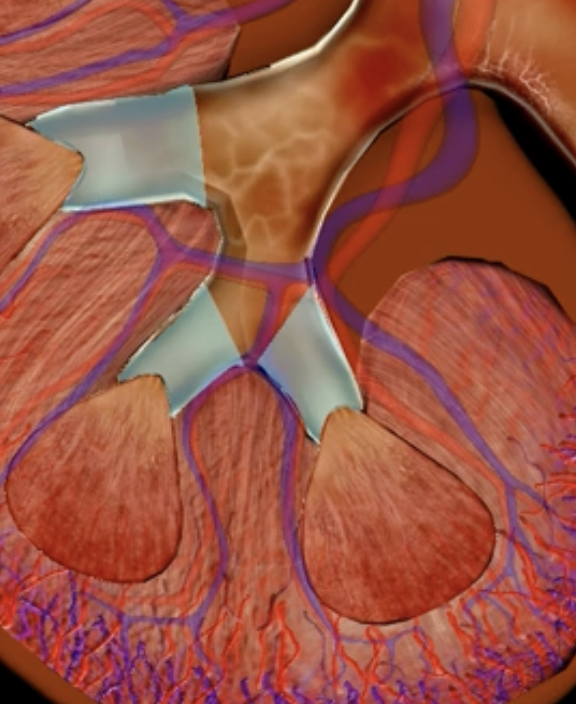

minor calyx

teal

major calyces

blue

renal pelvis

minor and major calyces

renal medulla

renal pyramids

renal lobe